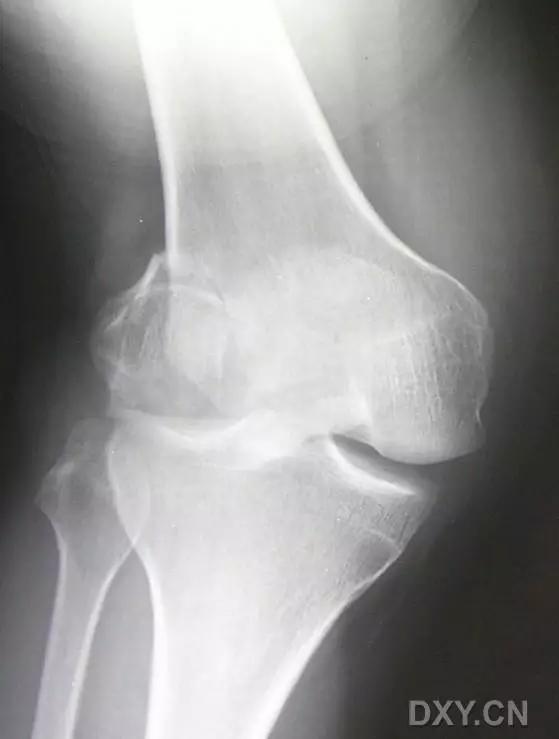

5. Hoffa 骨折

指股骨远端冠状面的骨折。

病例 1:一般股骨髁间、髁上粉碎骨折中含 Hoffa 骨折的不少见,但单纯后髁骨折则很少见。

正位片

侧位片